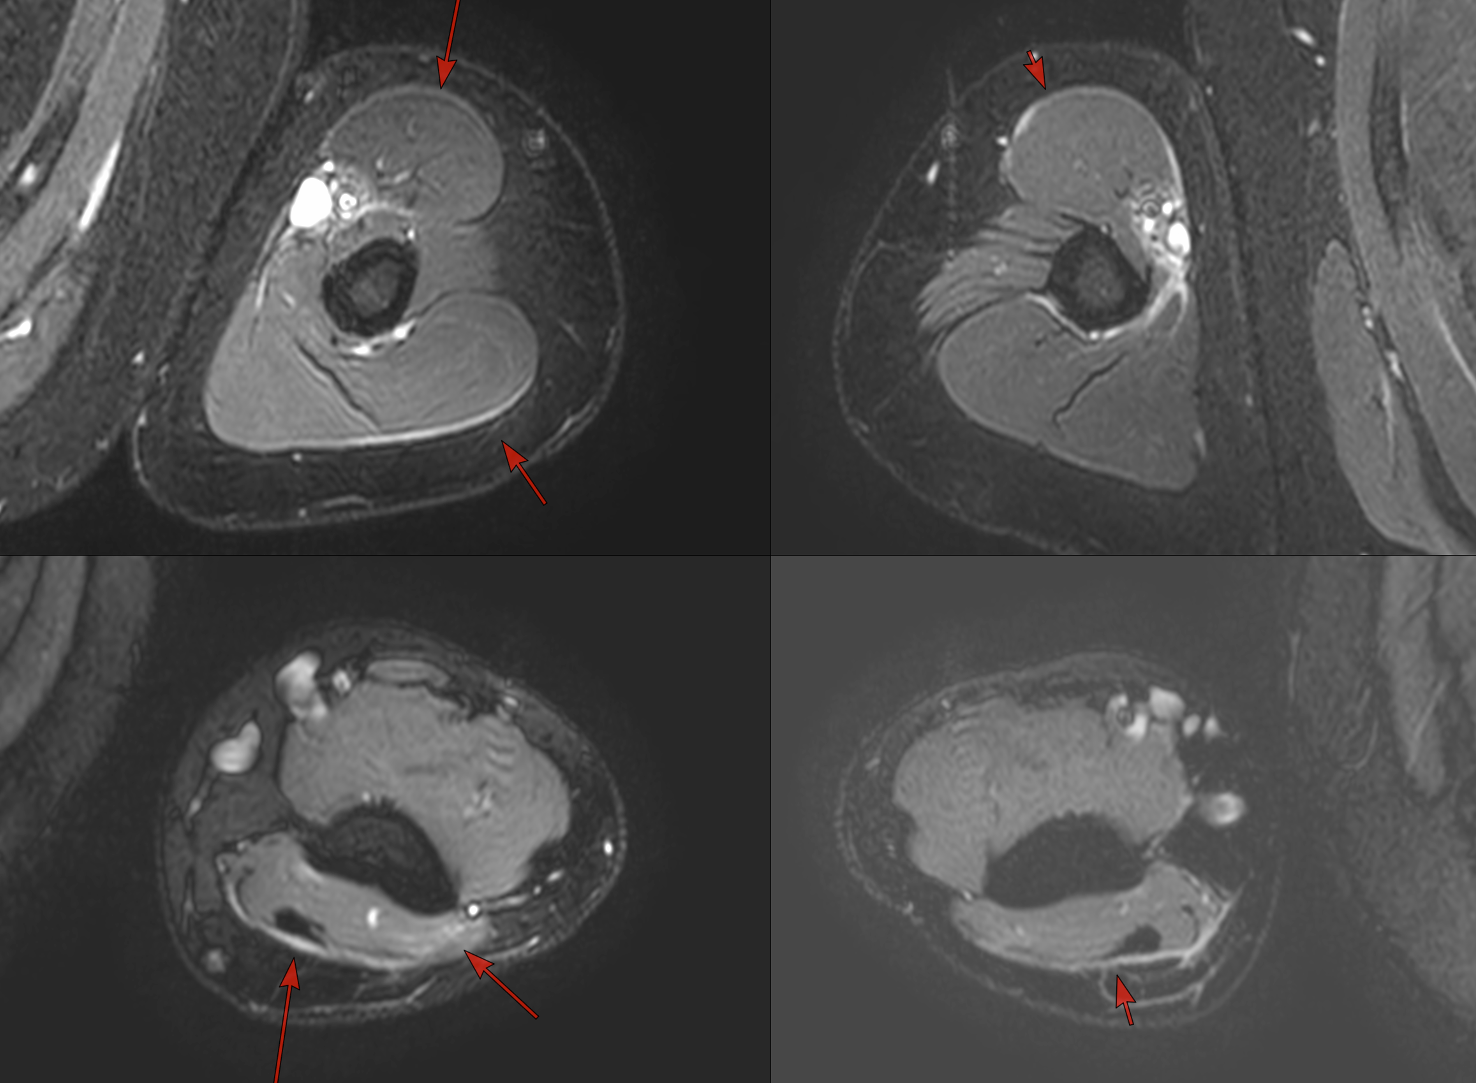

Case 62: The Symmetric Fascial Edema Pattern of Dermatomyositis

35-years old with dermatomyositis

35-years old man with dermatomyositis and limb pain on treatment came for a baseline myositis protocol MRI, which showed symmetric fascial edema as depicted in the images below.